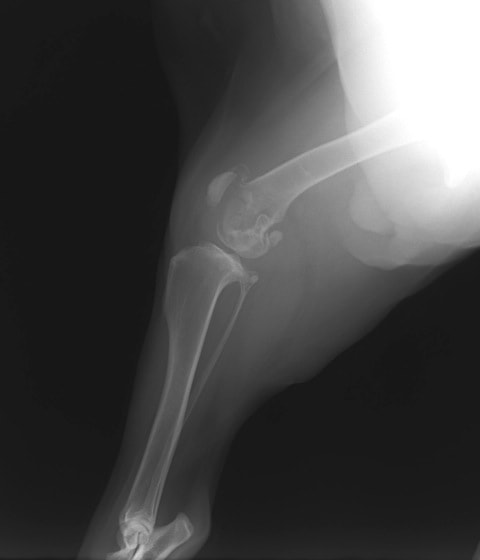

レントゲン検査

レントゲン検査所見から、骨もしくはその周囲組織に発生した腫瘍の可能性が考えられたため、病変部の細胞診検査およびジャムシディ生検針を用いた病変の骨生検を実施した。病理組織検査の結果、非上皮性の悪性腫瘍である“肉腫”と診断された。

内科治療に反応が乏しい四肢の跛行や疼痛は、本症例のように腫瘍が原因となっていることがあるため、レントゲン検査、骨生検等積極的に原因追及のための検査を実施することが必要である。骨の破壊を起こす悪性腫瘍は、非常に強い痛みを伴い、消炎鎮痛剤を用いても痛みを抑えることが困難となる。痛みの除去および腫瘍の治療のために断脚手術や抗がん剤等が必要となる場合があり、似た症状を示す整形外科疾患等とは治療法・予後が異なるため、その鑑別は重要である。